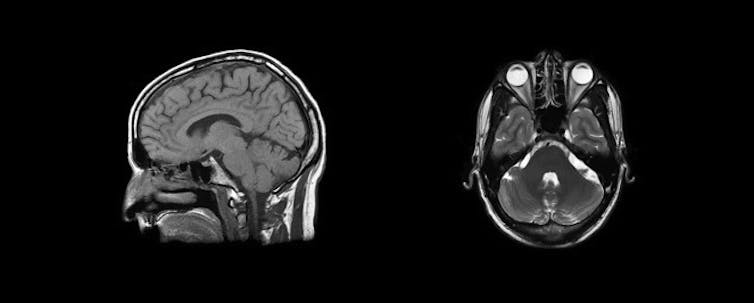

Your brain and other soft tissue are 60-70% water compared to your bones which are only 30% water, so MRI is much better at mapping soft tissue. As you can see in the MRI image below, the aqueous humour of the eye shows up white, while skull bones are comparatively dark.